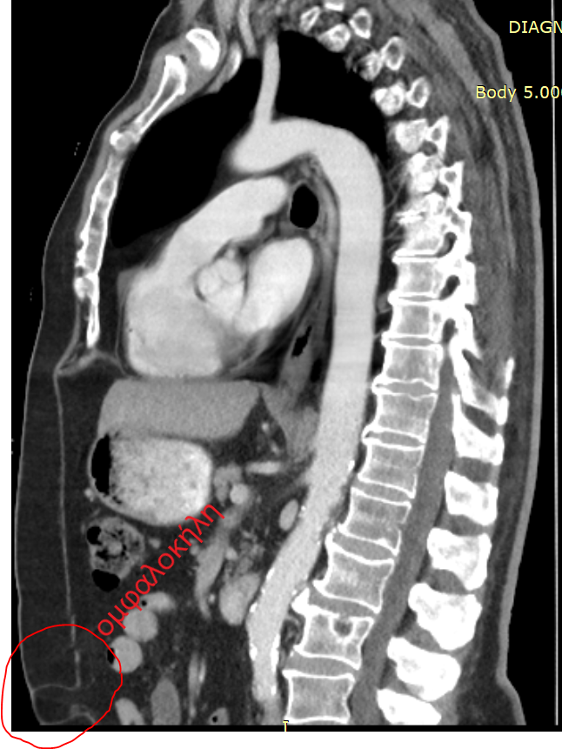

- & ευμεγέθη ομφαλοκήλη.